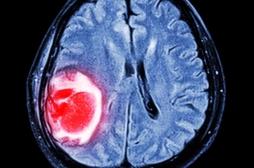

LES MALADIES

J'AI MAL

J ai Mal Bras et mains Bras et mains Tête et cou Torse et haut du dos Jambes et pied